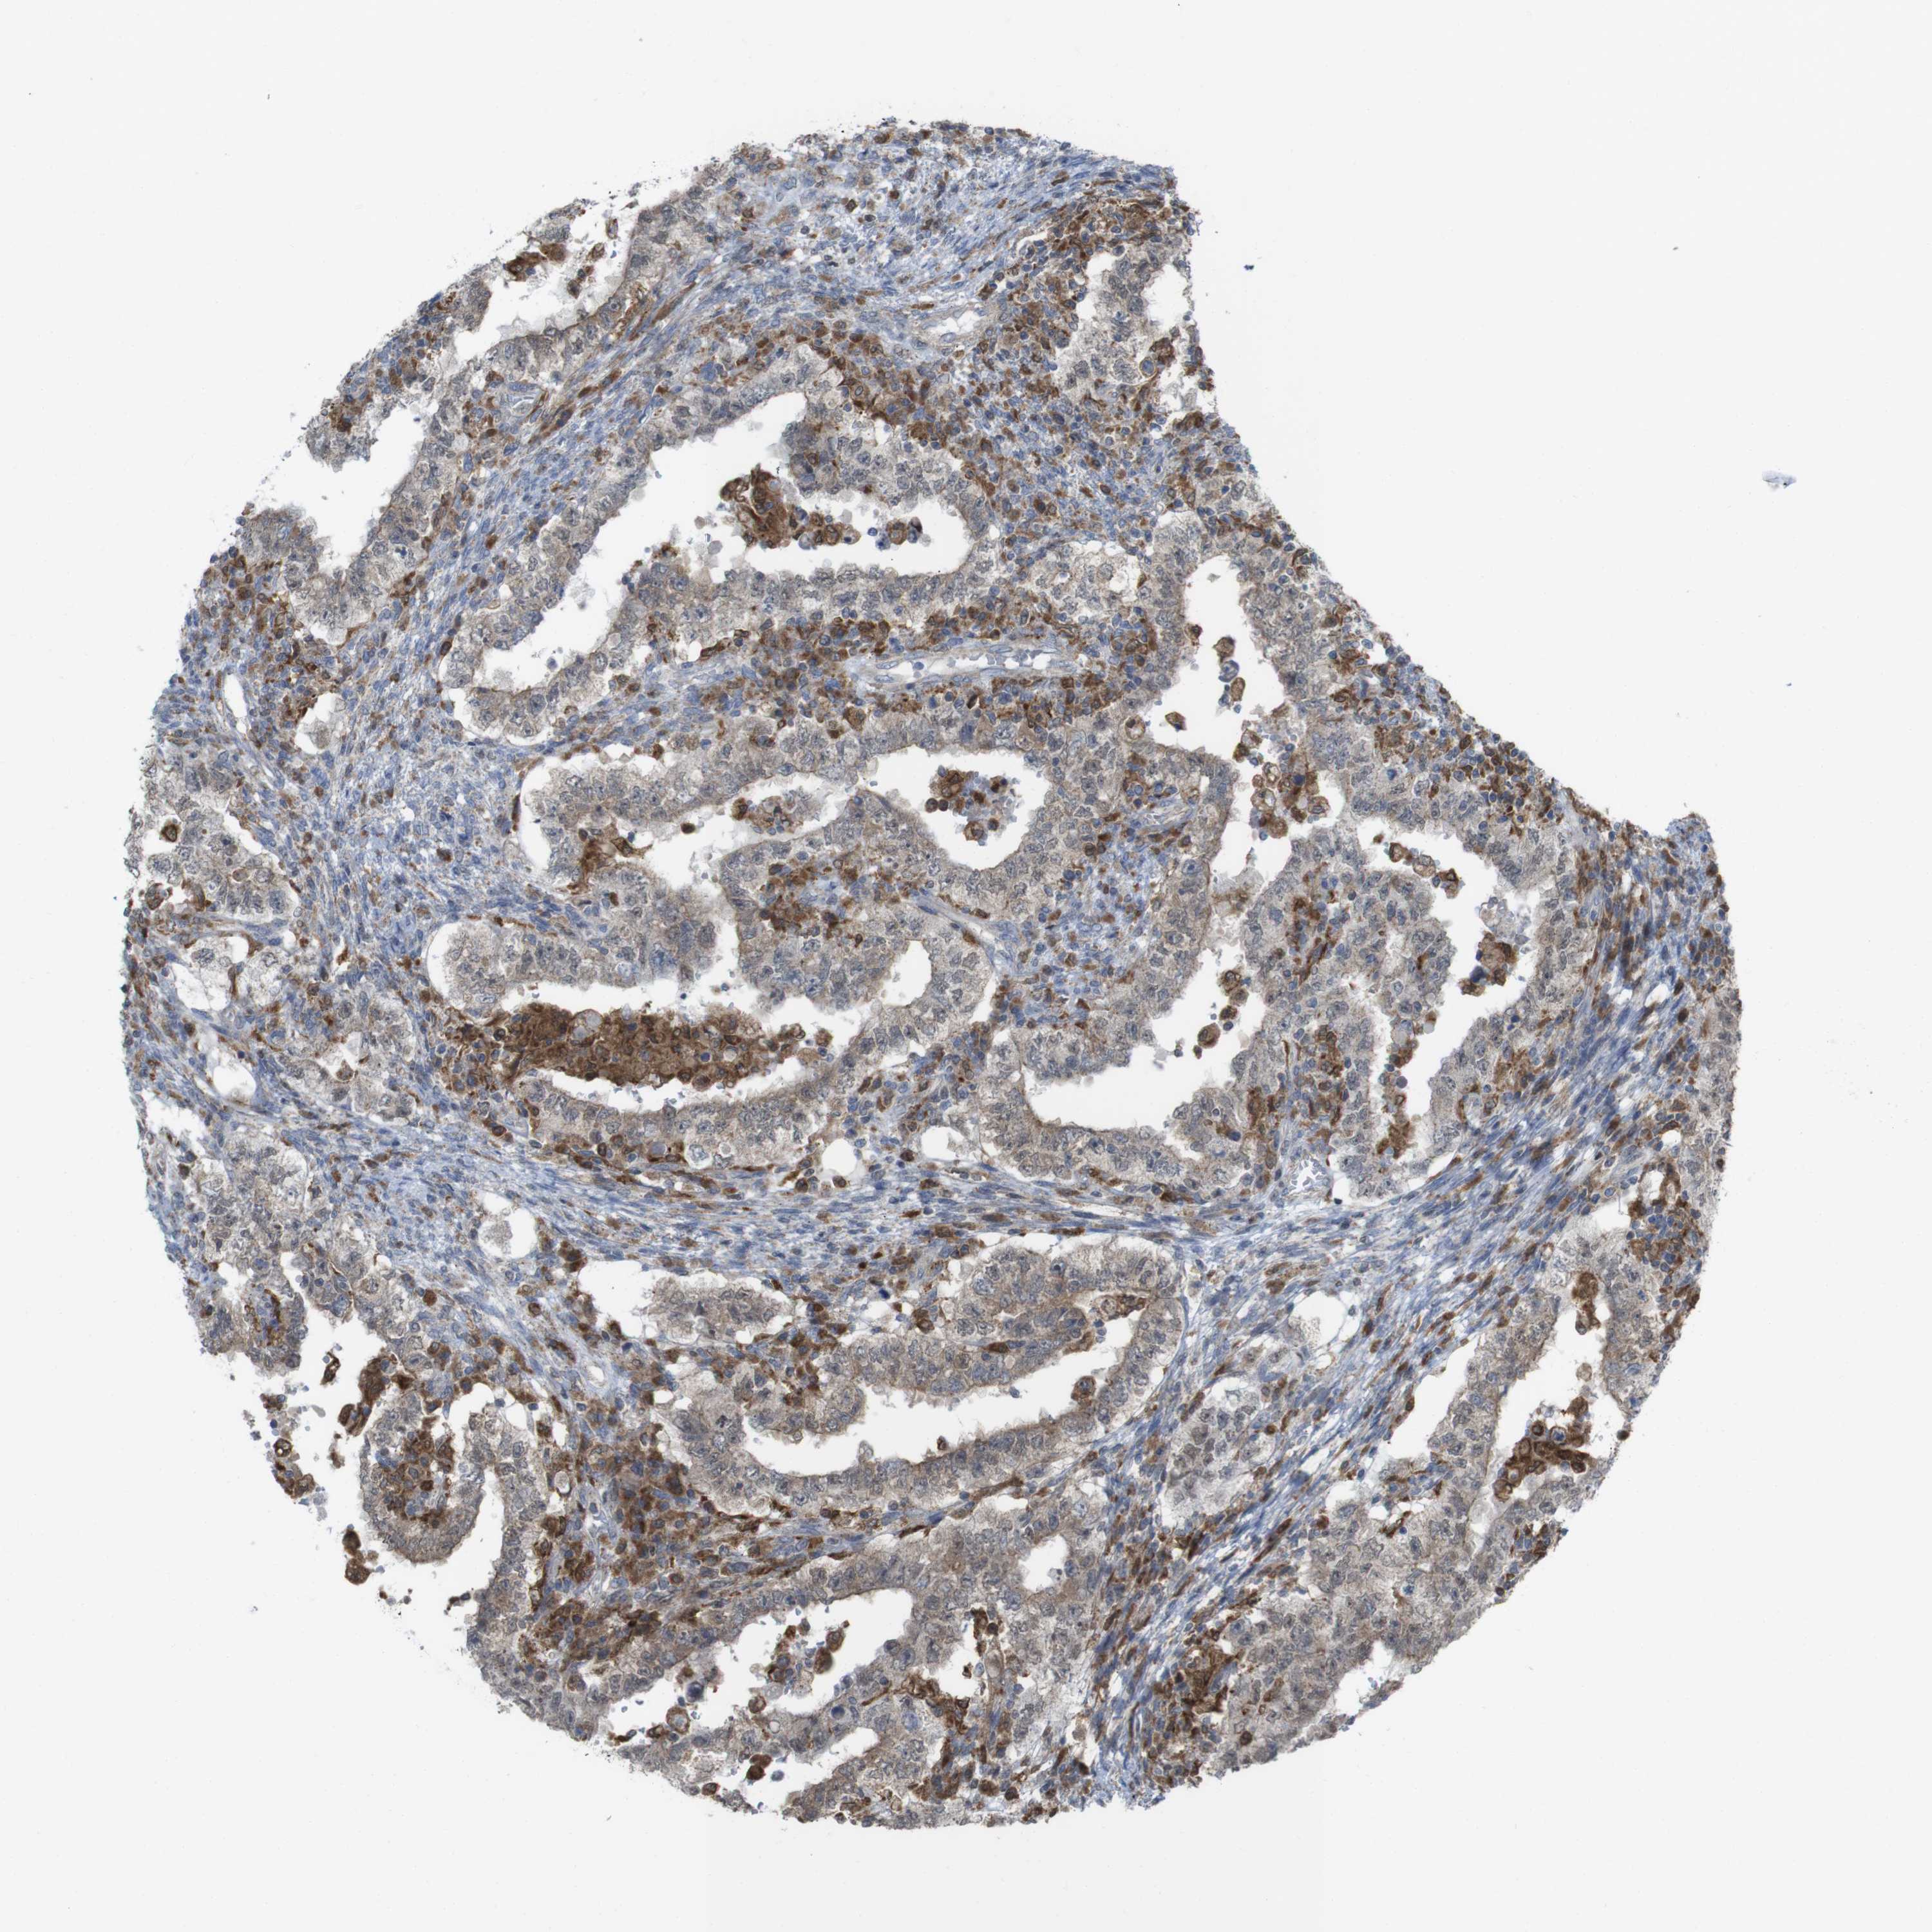

TESTIS CANCER - Protein expressioni

A mouse-over function shows sample information and annotation data. Click on an image to view it in a full screen mode. Samples can be filtered based on level of antibody staining by selecting one or several of the following categories: high, medium, low and not detected. The assay and annotation is described here.

Note that samples used for immunohistochemistry by the Human Protein Atlas do not correspond to samples in the TCGA dataset.

Antibody stainingi

Antibody staining in the annotated cell types in the current human tissue is reported as not detected, low, medium, or high, based on conventional immunohistochemistry profiling in selected tissues. This score is based on the combination of the staining intensity and fraction of stained cells.

Each image is clickable and will lead to virtual microscopy that enables deeper exploration of all samples and also displays staining intensity scores, fraction scores and subcellular localization as well as patient and tissue information for each sample.

Antibody HPA001863

Antibody HPA001890

Antibody CAB010469

Antibody CAB013225

Carcinoma, Embryonal, NOS

Seminoma, NOS